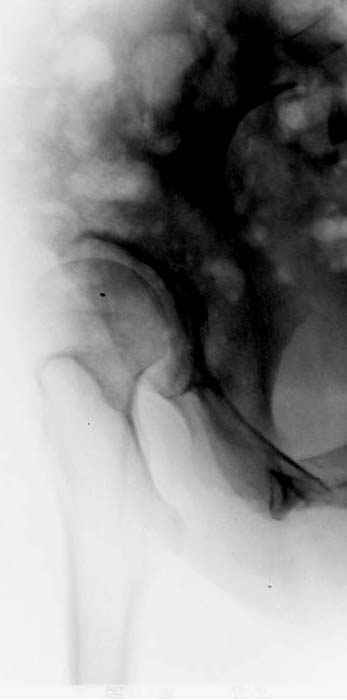

До операции #1

№ 1-3 до операции